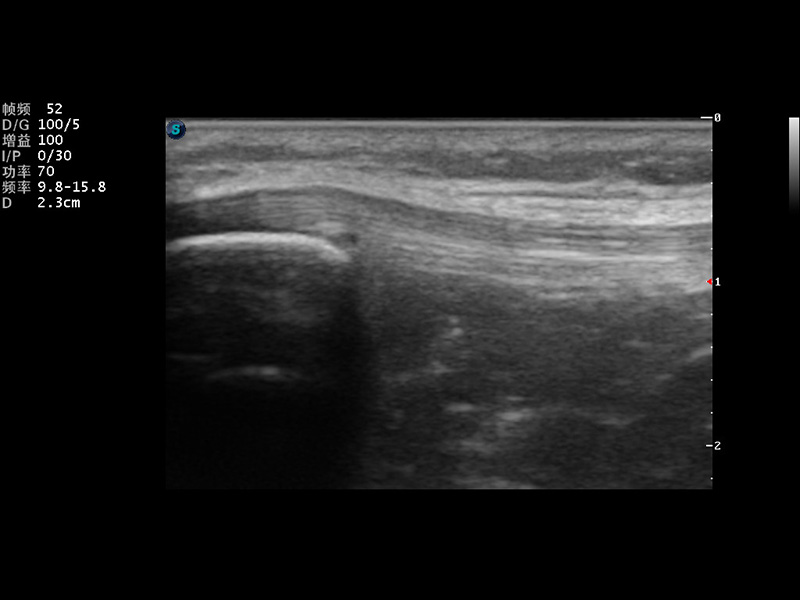

成像技术

VIS平台设计